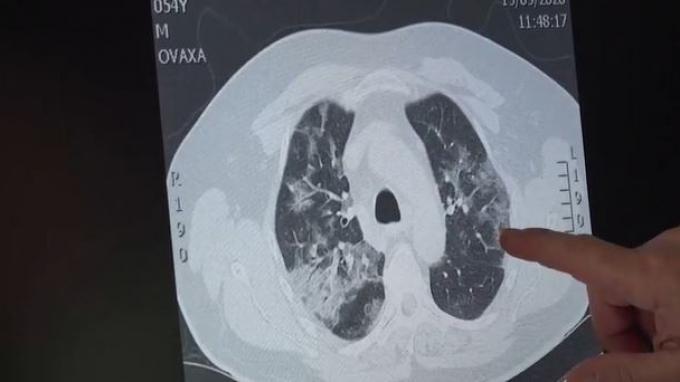

Peneliti China telah menemukan kantung berisi cairan atau serpihan di paru-paru pasien yang terinfeksi corona.

Hasil pemindaian menunjukkan bahwa mereka yang sembuh dari corona bisa mengalami penurunan fungsi paru-paru.